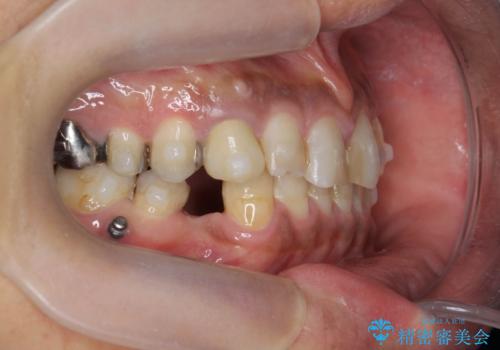

- 長年虫歯の治療を受け続けたことで銀歯・コンポジットレジン修復だらけになってしまい、今後の見た目や歯を大切にするためにセラミック治療矯正治療を希望され来院されました。

マイクロスコープを用いた精密根管治療やセラミック治療、マウスピース矯正治療を一つの医院で行うことのできる当法人ならではの総合歯科治療を実践していきます。

- 約330万円 (セラミック治療 矯正治療 インプラント治療含む)費用は治療当時の料金となります